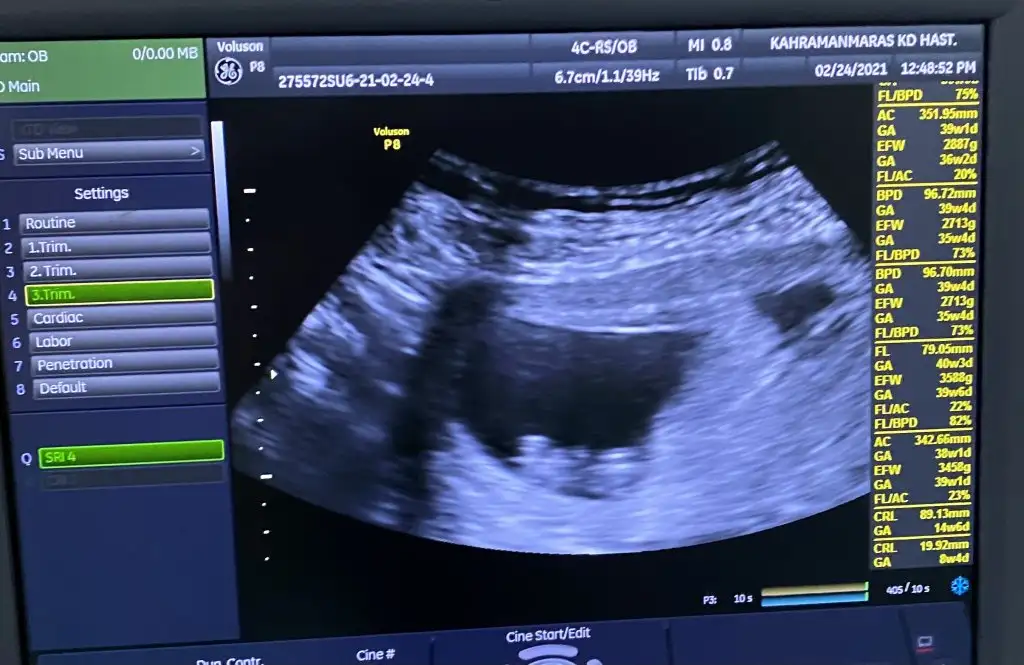

Kızlar dün doktora gitmiştim yine. Yeni kanama alanı gözükmüyor çok şükür.

İnşallah son olmuştur artık 🤲😅

9+3 vajinal, ilk defa bebeğe benzettim koca kafasiyla 😅 yorumlamak isteyen 🤗